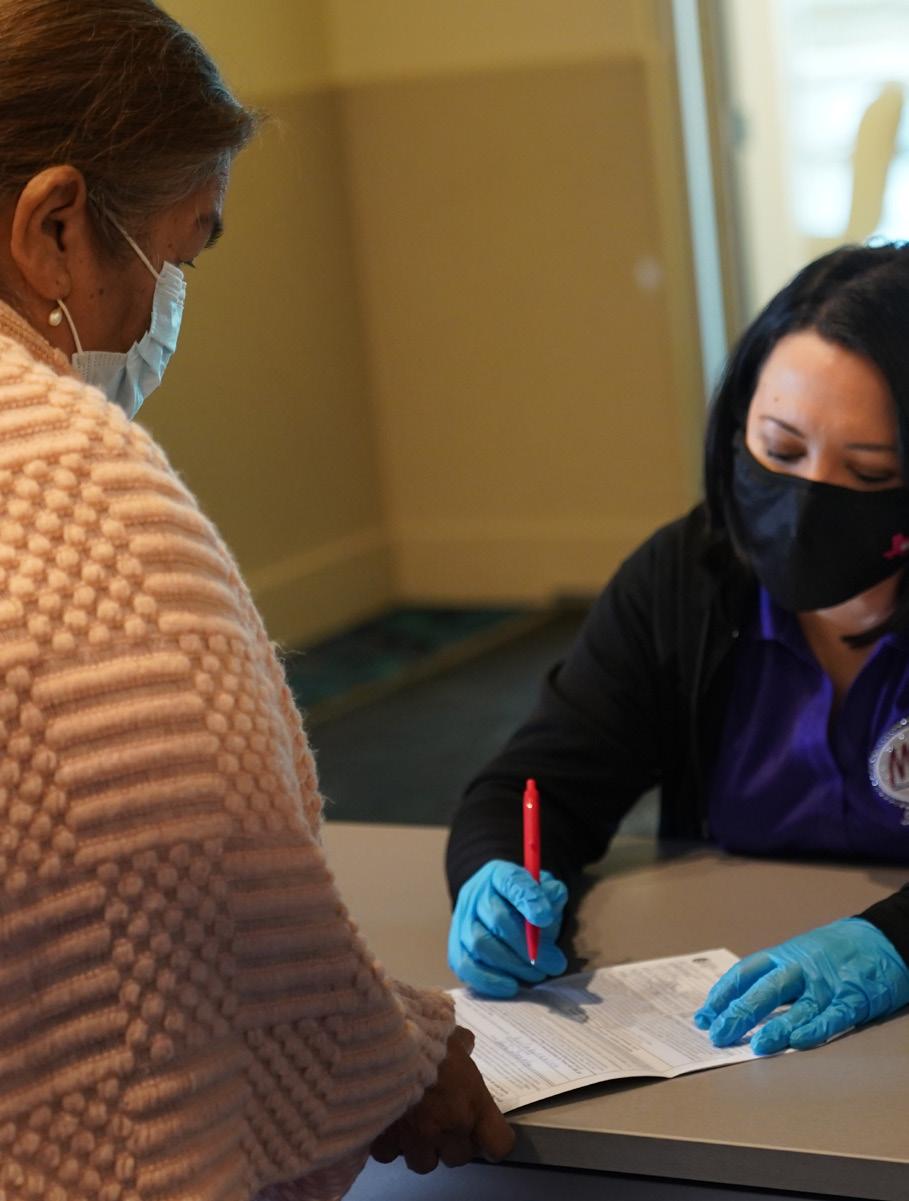

making a difference one vaccine at a time

To our fearless nurses, first responders, volunteers and registration teams: we thank you for your bravery, dedication and hard work. Thanks to you, the City of Mission, in partnership with Hidalgo County, Precinct 3 Commissioner Everardo “Ever” Villarreal, Sharyland ISD, and Mission CISD, has successfully vaccinated hundreds of people. It’s all in an effort to keep our community safe!

Throughout this pandemic, the City of Mission has been focused on protecting our community. We’re proud to protect and serve our All-America City during this challenging time. Mission health officials are working to get more people vaccinated as quickly as possible. Stay tuned for more community COVID-19 vaccination clinics headed to our city!